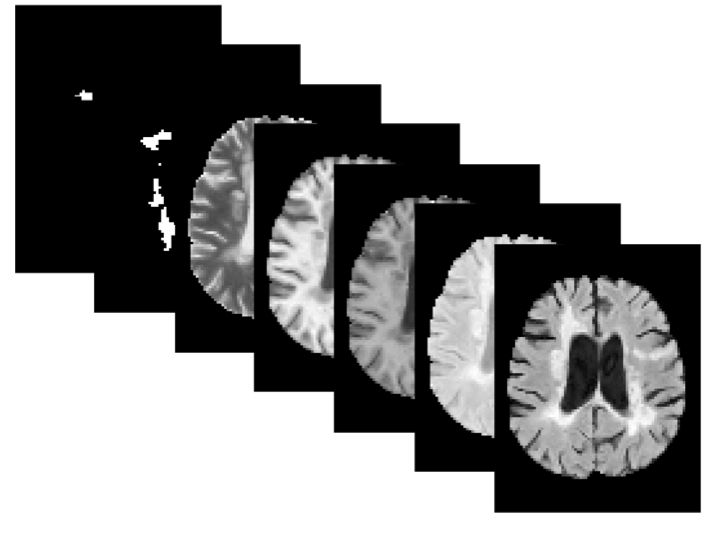

Precision medicine for chronic diseases such as multiple sclerosis (MS) involves choosing a treatment which best balances efficacy and side effects/preferences for individual patients. Making this choice as early as possible is important, as delays in finding an effective therapy can lead to irreversible disability accrual. To this end, we present the first deep neural network model for individualized treatment decisions from baseline magnetic resonance imaging (MRI) (with clinical information if available) for MS patients. Our model (a) predicts future new and enlarging T2 weighted (NE-T2) lesion counts on follow-up MRI on multiple treatments and (b) estimates the conditional average treatment effect (CATE), as defined by the predicted future suppression of NE-T2 lesions, between different treatment options relative to placebo. Our model is validated on a proprietary federated dataset of 1817 multi-sequence MRIs acquired from MS patients during four multi-centre randomized clinical trials. Our framework achieves high average precision in the binarized regression of future NE-T2 lesions on five different treatments, identifies heterogeneous treatment effects, and provides a personalized treatment recommendation that accounts for treatment-associated risk (e.g. side effects, patient preference, administration difficulties).